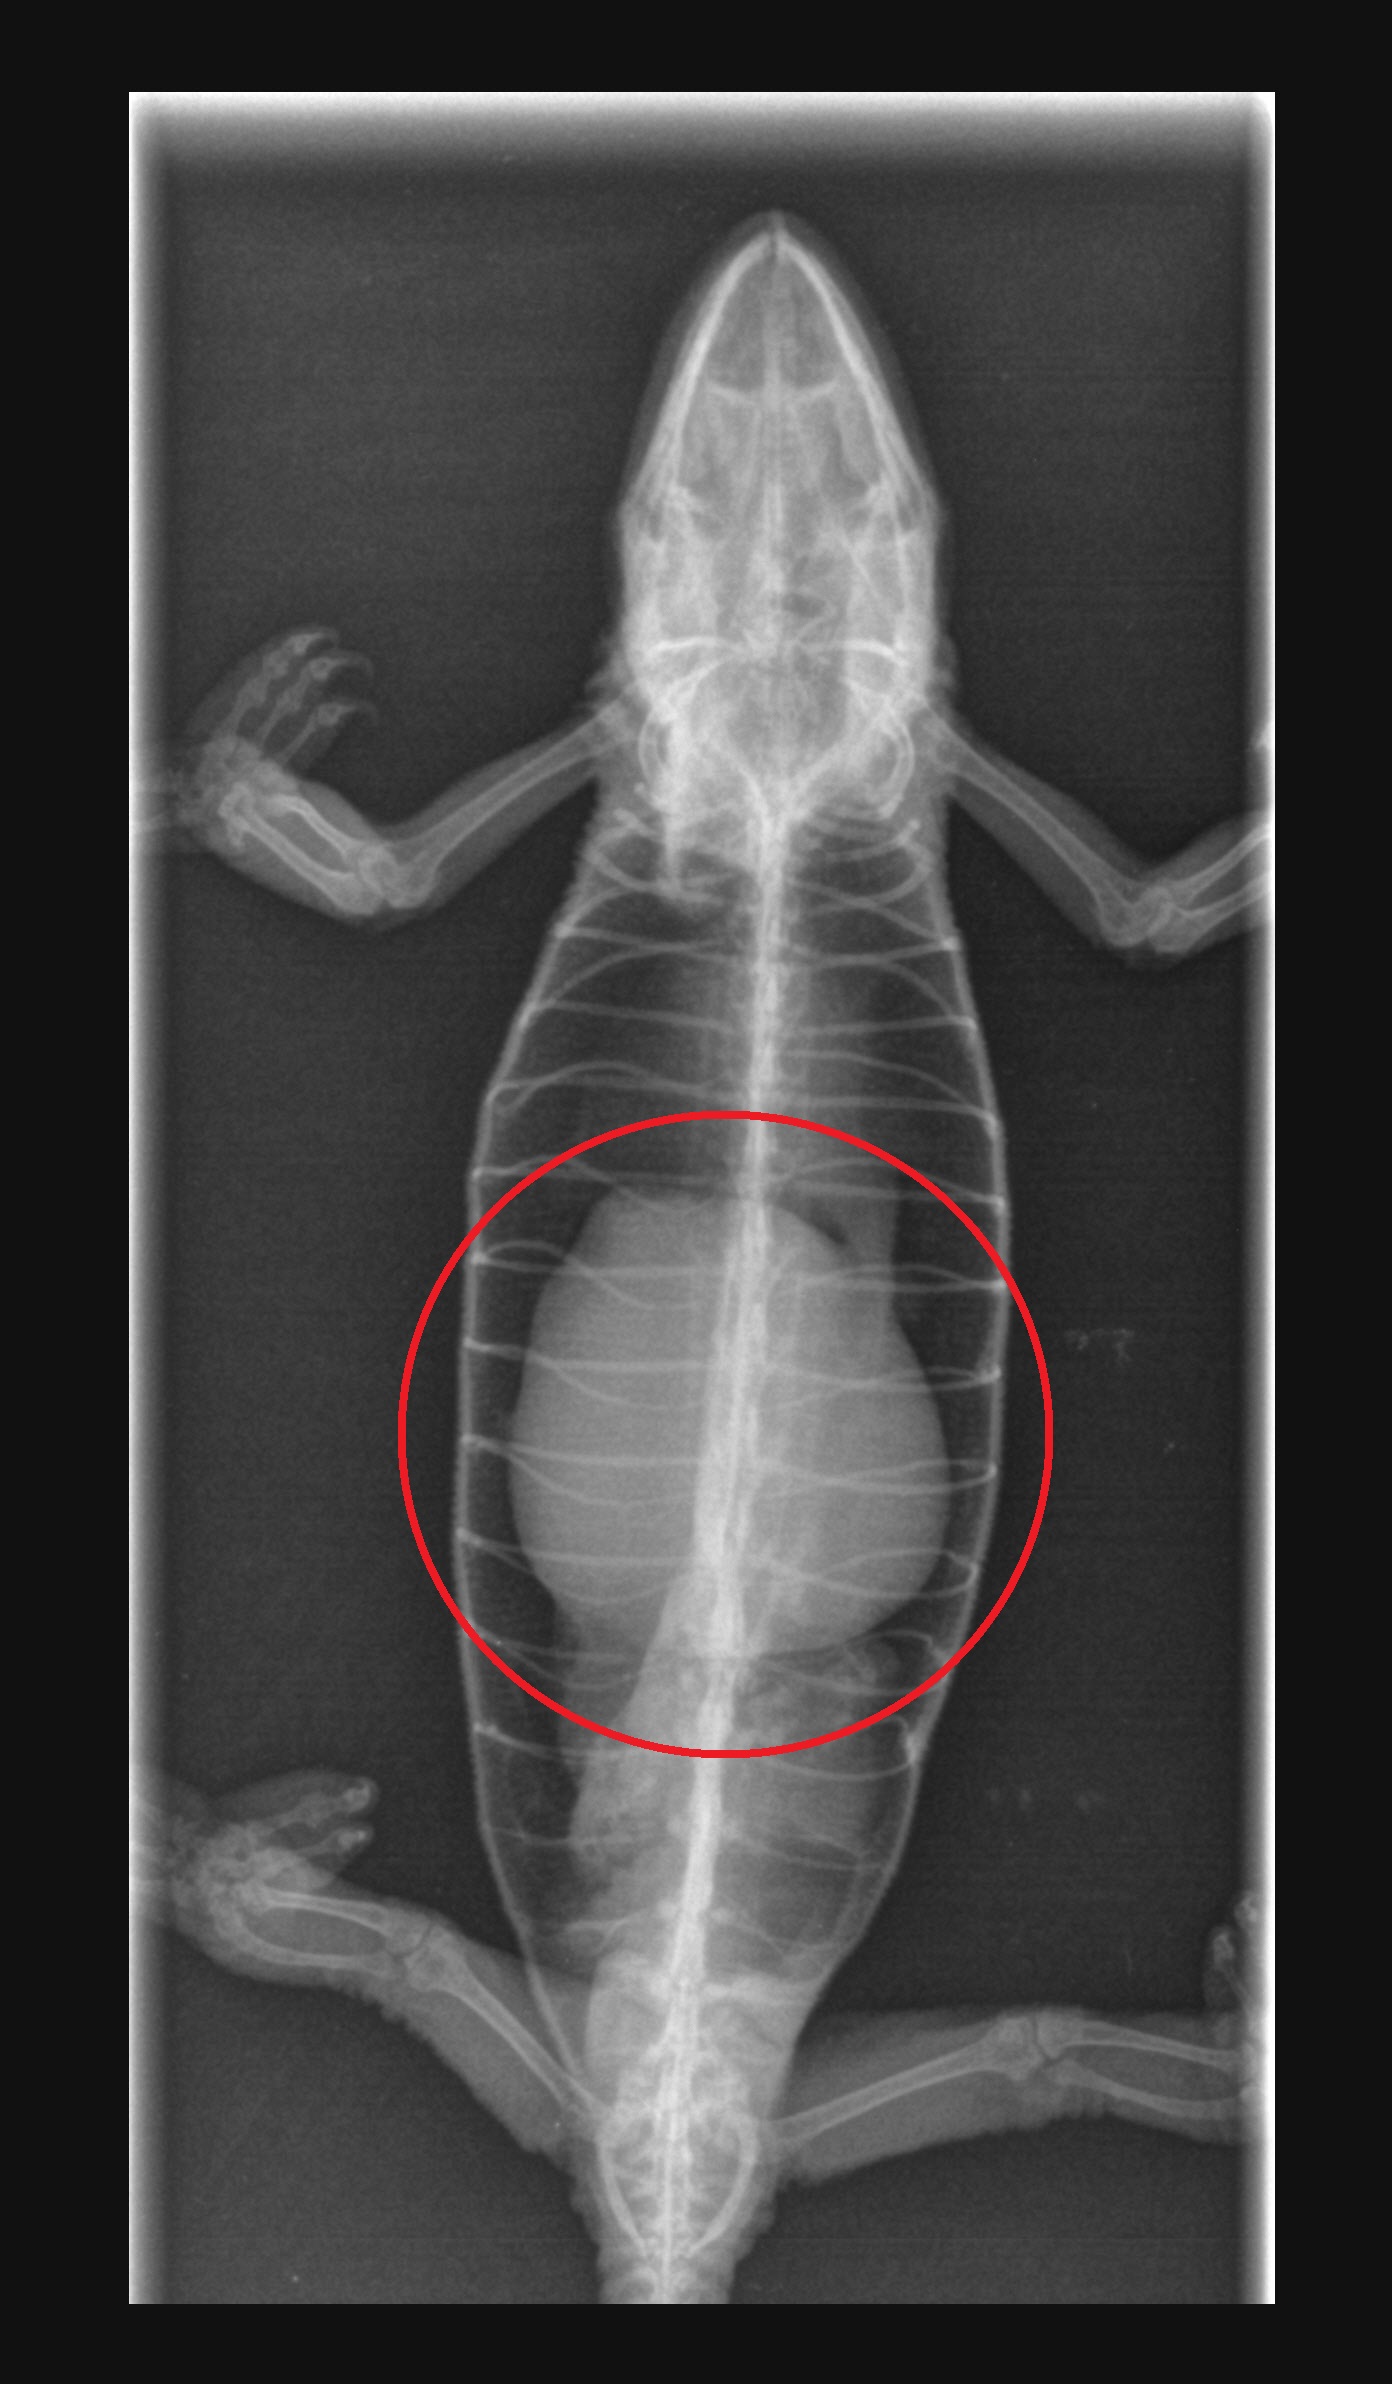

RTG: červeně je znázorněn útvar v dutině břišní.